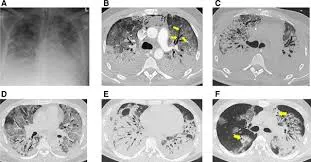

It is a medical imaging technique used in radiology to get detailed images of the body noninvasively for diagnostic purposes.

CT scanners use a rotating x-ray tube and a row of detectors placed in the gantry to measure X-ray attenuations by different tissues inside the body.

The multiple X-ray measurements taken from different angles are then processed on a computer using reconstruction algorithms to produce tomographic (cross-sectional) images (virtual “slices”) of a body.